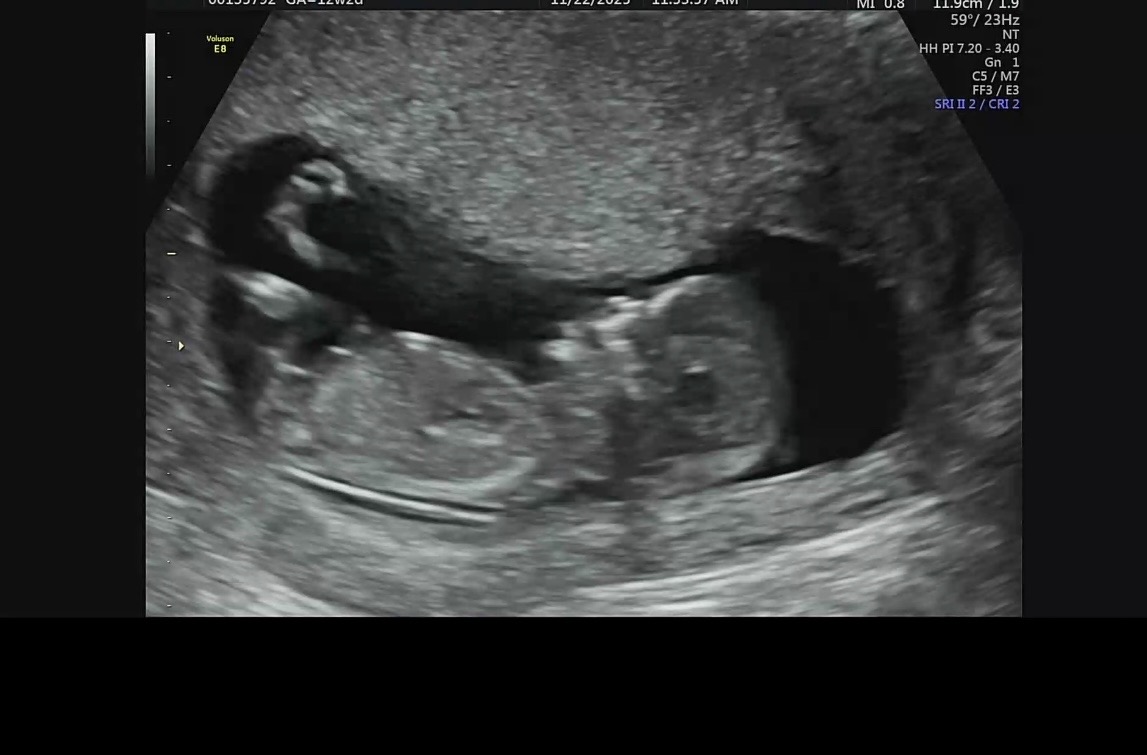

12주 2일에 1차 기형아검사 하고 왔습니다. 한참을 보시더니 목투명대 3.6나왔다고 니프티 하자고 하셨어요. 제가 융모막이나 양수검사 이야기했더니 딱히 권유안하시고(이 병원에서는 융모막이나 양수검사를 안해주는 느낌인지..뭔지는 모르겠어요) 니프티 하자고 반복해서 이야기해서 니프티 결과 기다리는 중입니다. 니프티 검사를 기다리는 중이라 다른 병원에 양수검사(16주) 예약해뒀는데 그냥 바로 융모막 검사를 하는게 나을뻔했나요? ㅠㅠ 융모막과 양수검사 중에 어떤 검사가 더 정확한가요? 코뼈는 보이는지도 한번 봐주시면 감사하겠습니다.. +니프티 결과! 니프티 결과 나왔어요. 주말빼고 일주일 정도 걸렸네요 검사결과는 다행히 저위험군으로 나왔습니다.. ㅠㅠ 그동안 정말 마음고생 많이 하고 안좋은생각도 했는데 아기한테 미안하네요. 어떤 글에서 아기는 우리의 생각보다 강하다는 말을 보고 위로를 많이 받았어요. 저와 같이 애타게 결과 기다리고 계계실 분들도 아기들은 잘 자라고 있을테니 힘내시길 바랄게요!

지금 둘찌임신중입니다. 첫째때 목투명대 4mm 쿼드에서도 다운증후군 1:3으로 초고위험군이였구요 놀란마음에 니프티해서 정상나왔습니다!! 지금 발달 상위에해당하는 아주건강한 2살이 되어있답니다. 니프티결과보고 결정하셔도될거같아요ㅎㅎㅎ 초음파로 코뼈도 보이는거같구요! 첫째때는 양수,융모막이 정확하다고해도 유산의 위험성도있고 니프티결과 정확도높아서 병원에서 딱히 권하진않았어요 너무 걱정되시겠지만 조금기댜려보는것도 좋을거같아요😃